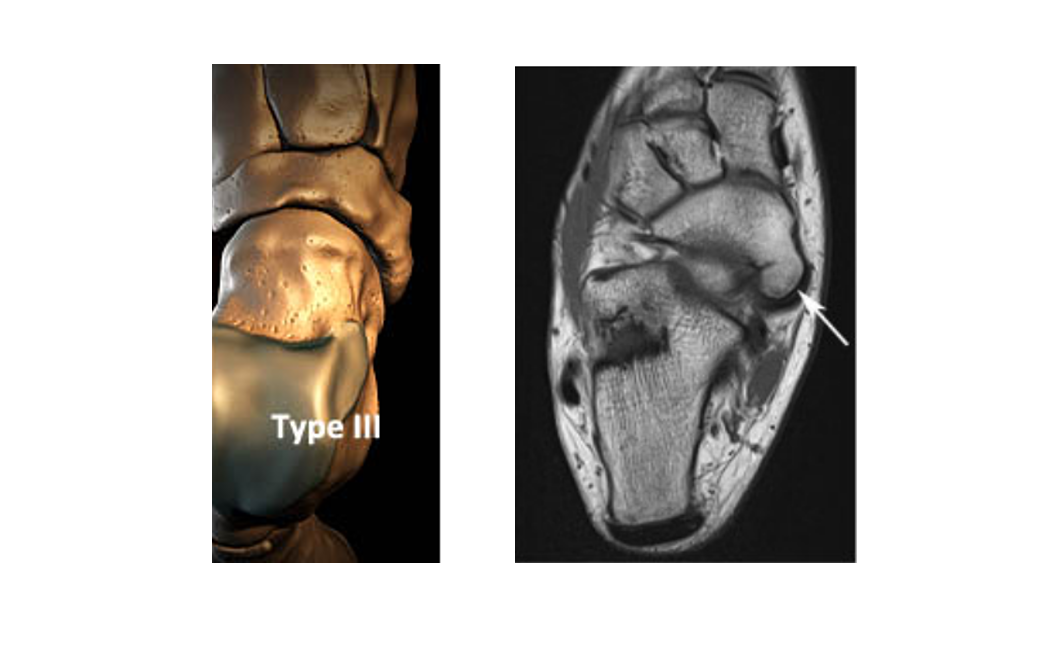

«МРТ голеностопного сустава»

На вебинаре будет рассмотрена анатомия голеностопного сустава и наиболее частые анатомические варианты, которые могут послужить причиной интерпретационных ошибок.